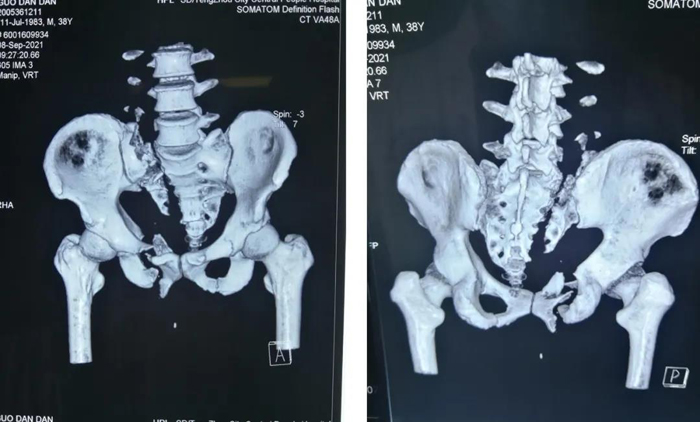

術前三維重建CT

該患者屬于多發傷,在我院ICU監護。術前,我們制訂了周密的手術計劃。林峰主任醫師主持術前討論,創傷一科全體醫生參加。骨盆骨折屬于C1.3,經骶骨2區骨折的骶髂關節脫位,如果采用切開復位會造成大量出血,此患者還需要行鎖骨骨折切開復位內固定,跟骨骨折切開復位內固定,手術創傷非常大,患者很難耐受。所以,我們選擇骶髂螺釘+前后路infix對骨盆骨折微創治療,最大限度地減少手術創傷,促進患者康復。